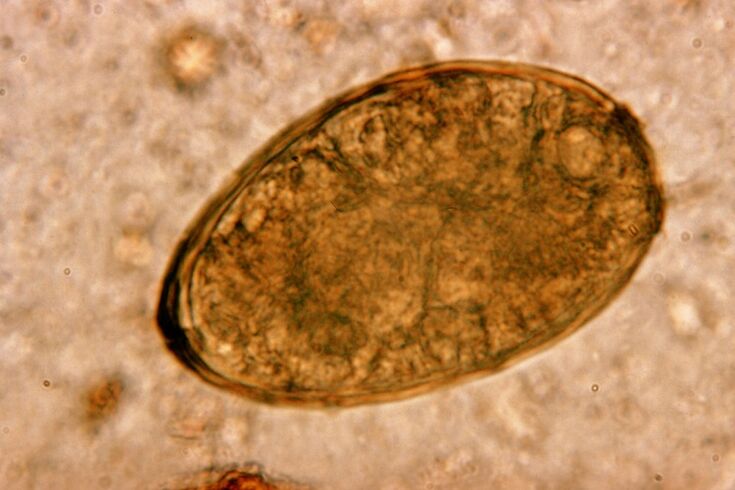

Dumaloq qurtlar, dumaloq qurtlar, jonli va ichaklarda takrorlash. Ular bilan infektsiya tanaga ovqat yoki qo'llar va infektsiyalangan shaxs tomonidan ishlatiladigan qo'llar va narsalar bilan kiradi. Tuproq, mevalar, sabzavotlar, pishirilgan go'sht va baliq - bularning barchasi gelmint tuxumlarini inson tanasiga kiritishi mumkin.

Bilishga arziydi! Dumaloq qurtlar quruq yo'talni qo'zg'atadi. Qon aylanish tizimi orqali ularning lichinkalari nafas olish organlari - bronx, traxeya, o'pka - retseptorlarni g'azablantiradi va bu simptomni qo'zg'atadi. Lichinkalarning tanadagi migratsiyasi davri bir-ikki haftadan ikki haftagacha.

Askar

Sumaloq qurtlar juda keng tarqalgan, shuning uchun askariyent fonida yo'tal - bu odatiy hodisa. Dumaloq qurtlar bilan infektsiya gelmashriasiyalar uchun an'anaviy yo'nalishlar orqali sodir bo'ladi. Bularga tuproq bilan aloqa qilish, evazsiz meva va sabzavotlar va iflos qo'llarni iste'mol qiladi.

Astaris Lichinkalar muammoni nafas olish tizimining to'qimalariga mexanik ta'sir ko'rsatadigan mexanik ta'sir ko'rsatadi. Bu parazitning migratsiya bosqichi paytida sodir bo'ladi. Dumaloq qurtlarning insonning nafas olish tizimiga ta'sirining mexanizmi va ketma-ketligi quyidagicha.

Bir marta oshqozon-ichak traktida, ularning fermentlari va ovqat hazm qilish sharbati ta'siri ostida dumaloq qurtlar, tuxumdonlar ta'siri ostida, lichinkalarga aylanib, qobiqlarini to'kishadi. Ikkinchisi ichak devoridan qon oqimiga kirishi qobiliyatiga ega. Shundan so'ng ular butun tanadagi qon orqali olib boriladi - jigar, yurak, o'pka va nafas olish yo'llari.

Traxea shilliq qavatida CIILia, lichinkalarni refleks harakatlari bilan yuqoriga ko'taradigan kiliya bor. Bunday holda, retseptorlar jahldor va yo'tal, gelmintlarni og'izga otish yoki yutib yuboradigan va ichaklarga qaytishda uchraydi.

Ma'lumotingiz uchun! Assariasis bilan yo'tal odatda qisqa muddatli hodisadir. Ammo agar yuqtirish takrorlanadigan tabiatga ega bo'lsa, u deyarli doimiy bo'lib qolishi mumkin.